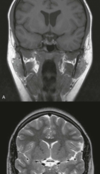

What is a T1 MRI scan, & how does it differ from a T2 scan?

By altering the sequence of pulses to which the protons are subjected, different properties of the protons can be assessed. These properties are referred to as the “weighting” of the scan.

By altering the pulse sequence and the scanning parameters, T1-weighted images and T2-weighted imagescan be obtained.

These two types of imaging sequences provide differences in image contrast, which accentuate and optimize different tissue characteristics.

What is a T1 MRI scan, and how does it differ from a T2 scan?

T1-weighted images show dark fluid and bright fat—ex: in the brain the CSF is dark;

T2-weighted images demonstrate a bright fluid and intermediate signal from fat—ex: in brain the CSF appears white.

REMEMBER> T2 H<strong>2</strong>0

What is it & which tissue might it derive from?

Which structures in the cerebral hemisphere is the lesion compressing?

Meningioma

tumors that arise from meningothelial cells

may become malignant, invading the brain and eroding the skull. In such cases, prominent edema may be present in the brain parenchyma, to the extent that the extra-axial nature of the tumor is no longer obvious.

temporal lobe

Why does gadolinium (Gd) enhance the lesion?

Enhancement with exogenous contrast material is now a routine part of MRI.

The material most widely used is a gadolinium chelate.

The gadolinium atom is strongly paramagnetic & acts to shorten the T1 relaxation time of nearby water protons in blood. it doesn’t pass the blood-brain barrier> very useful in detecting disruption of the blood-brain barrier by neoplasm, infection, trauma, and infarction.

The T1-shortening effect is also used for rapid MRA, which is performed in a fast scanning protocol after the bolus injection of a contrast agent. In the brain, bolus injection of gadolinium with repeated echo planar imaging (EPI) has been used to image perfusion 31 and the blood volume of tumors